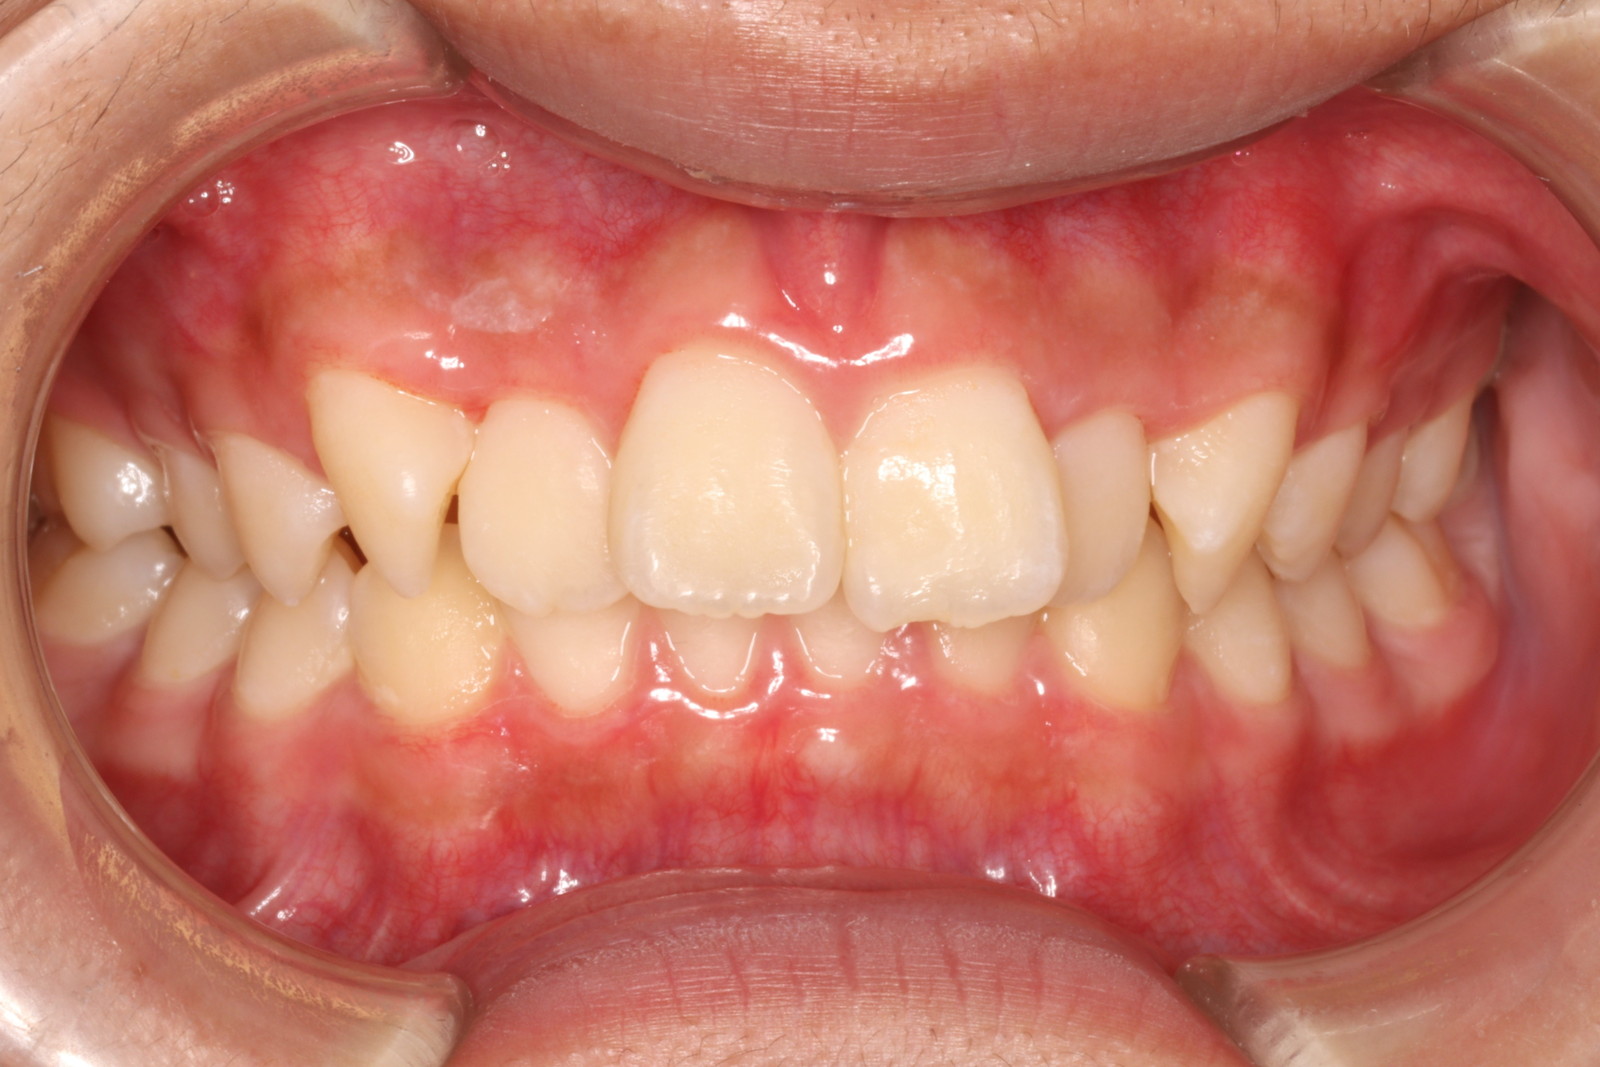

矯正治療後、整えた歯並びが徐々に元に戻ってしまう現象を「後戻り」と言います。後戻りの原因の多くは、歯を保定する装置であるリテーナーの装着不足によるものです。後戻りしてしまうと、再治療が必要になり、また何年も治療期間がかかるのではないかと心配される方も多いでしょう。

しかし、後戻りした歯の多くは、部分的な矯正で済む場合もあります。歯列全体を矯正するよりも、費用も期間も少なく済むことが多いので、まずは当院にご相談ください。

状態を確認し、検査させていただいた後、正確な治療費や治療期間を契約前にお伝えいたします。無理に治療を勧めることはありませんので、どうぞお気軽にご相談ください。